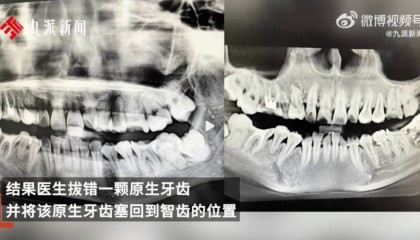

近日,安徽一名女子在网络自述“被安庆市立医院口腔科医生拔错牙齿并错误塞回”,后将个人简介改为“在市立...

女子疑因拔错牙又被塞回坠楼身亡,多方回应

近日,一位网友发文称自己34岁妹妹在安徽安庆市立医院口腔科门诊拔智齿,结果医生拔错一颗原生牙齿,并将...